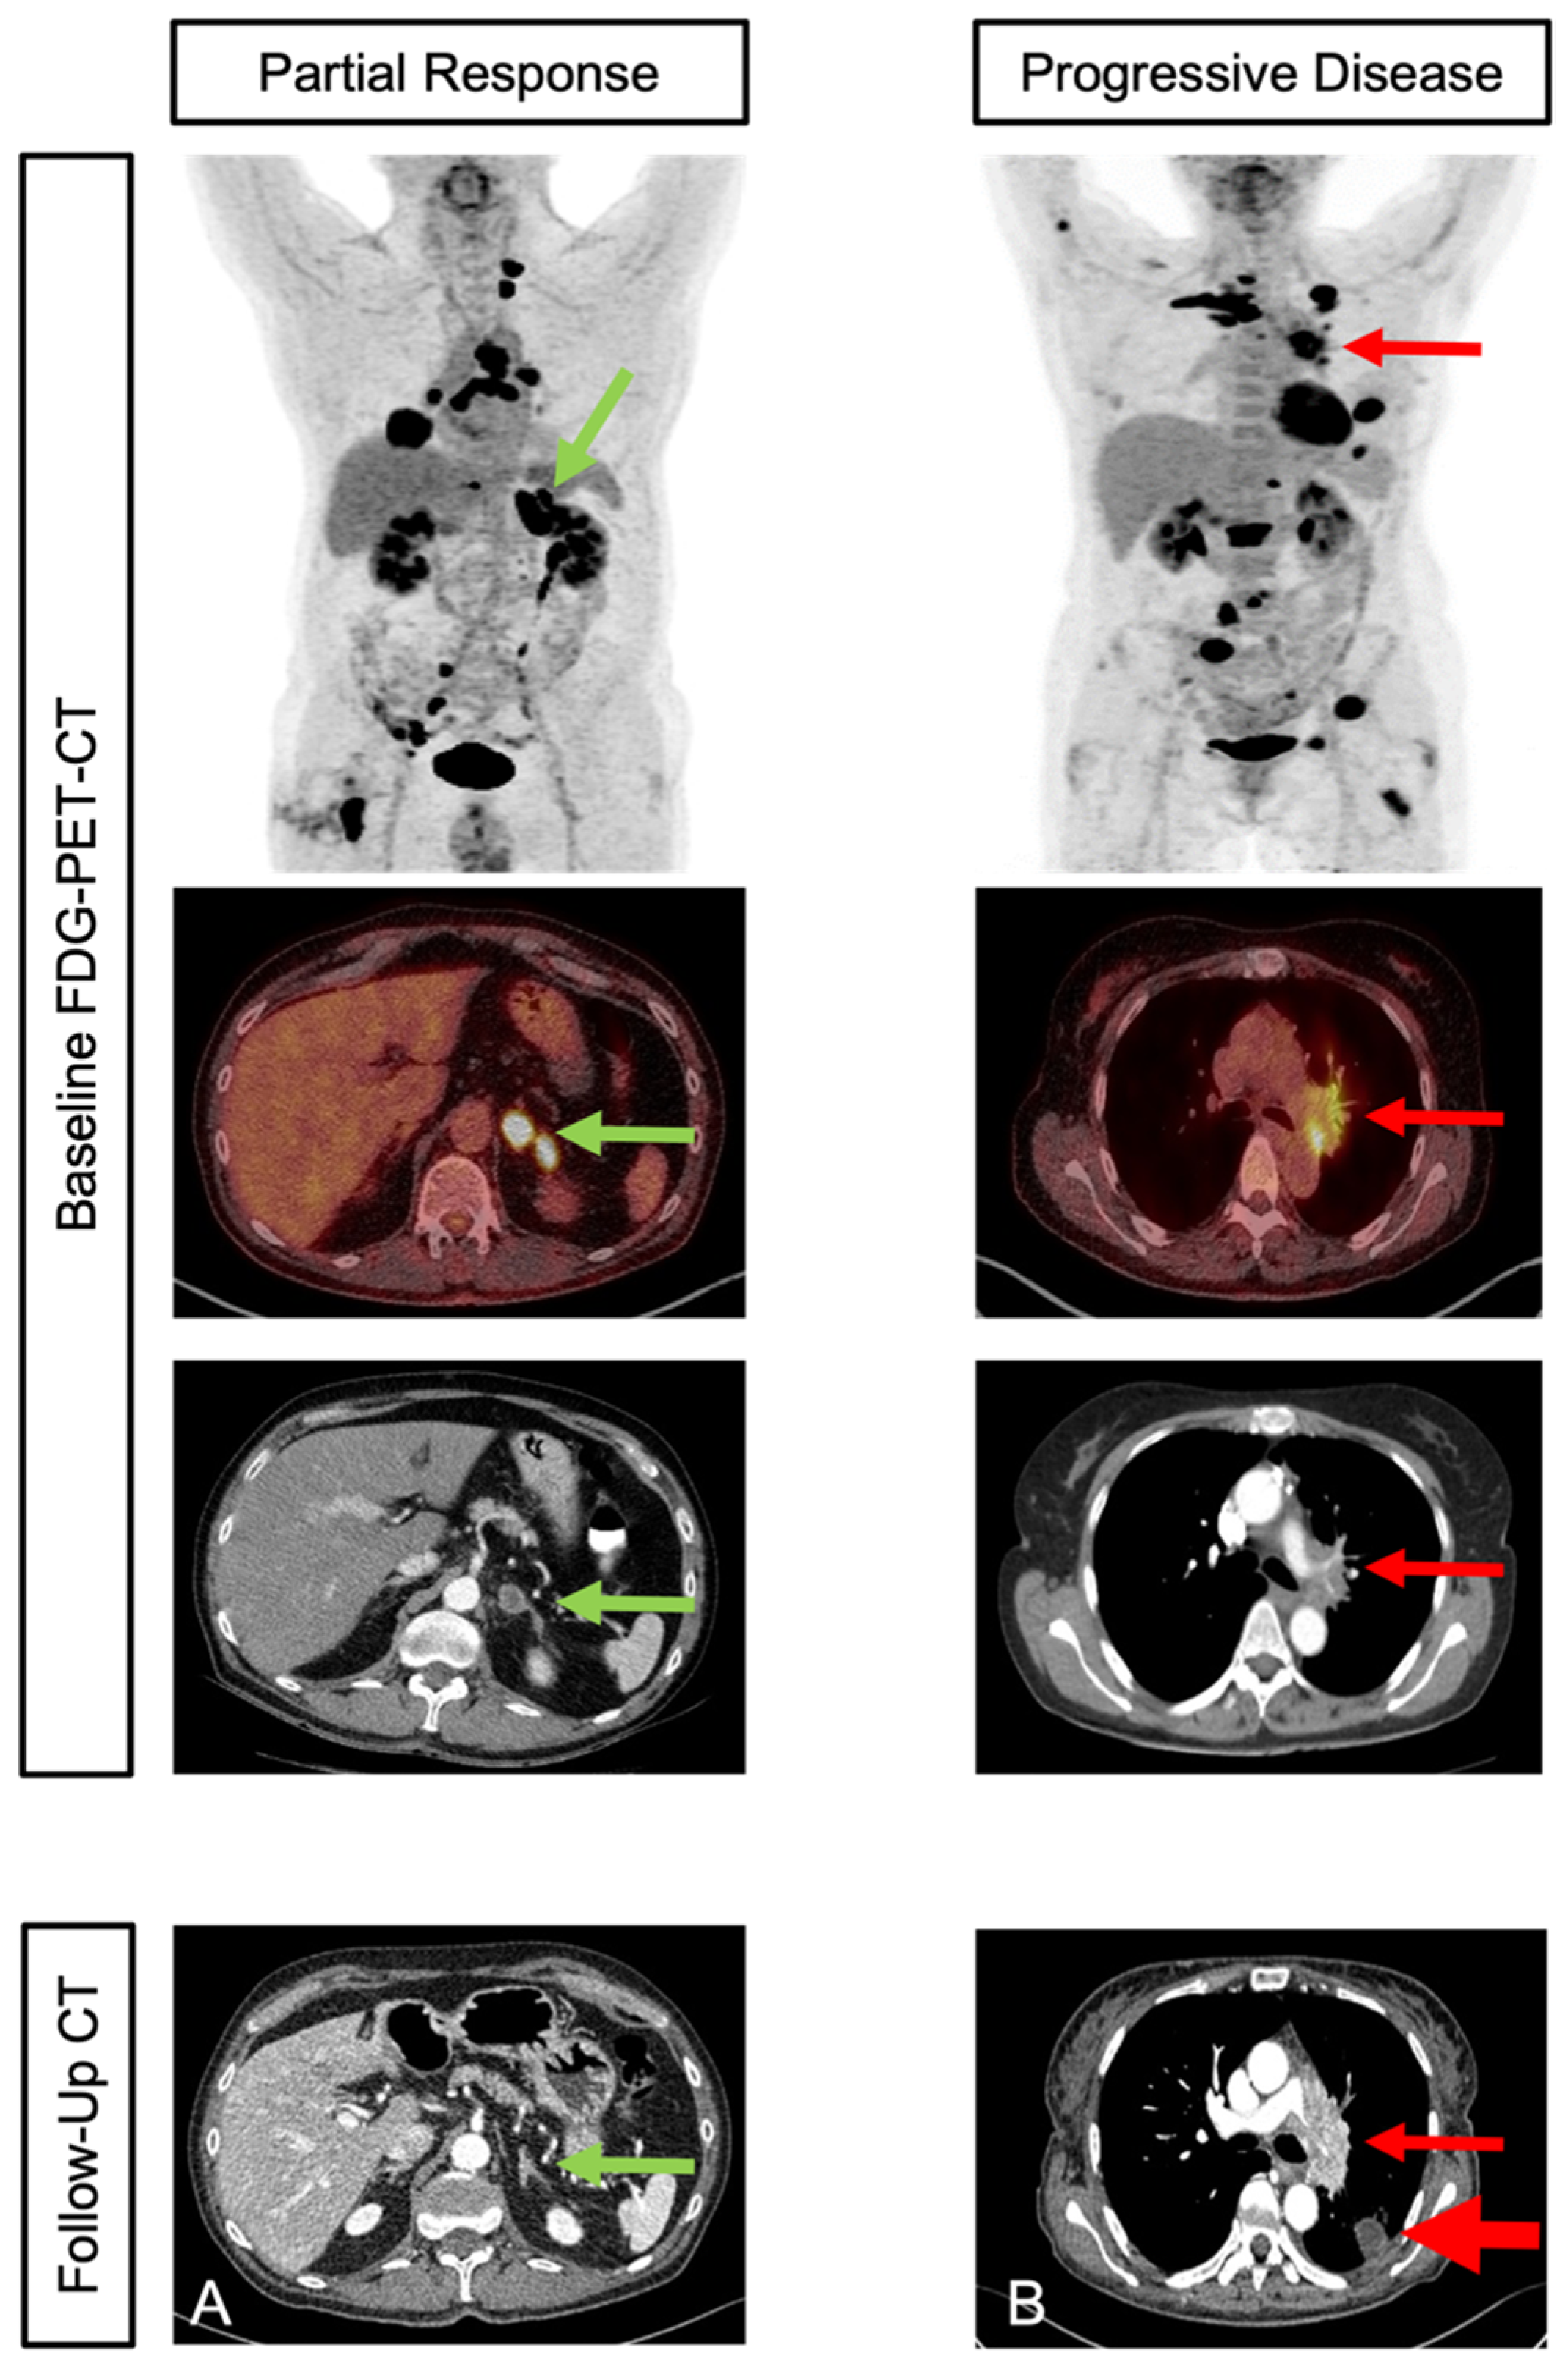

3.4. Outcome Prediction

3.5. Survival Analysis for PFS